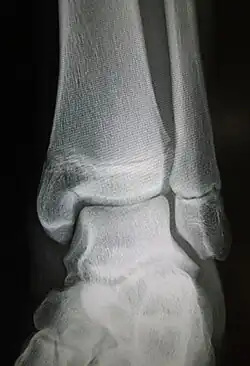

Maisonneuve fracture

Radiograph showing a Maisonneuve fracture of the proximal fibula

The Maisonneuve fracture is a spiral fracture of the proximal third of the fibula associated with a tear of the distal tibiofibular syndesmosis and the interosseous membrane. There is an associated fracture of the medial malleolus or rupture of the deep deltoid ligament of the ankle. This type of injury can be difficult to detect.[1][2]